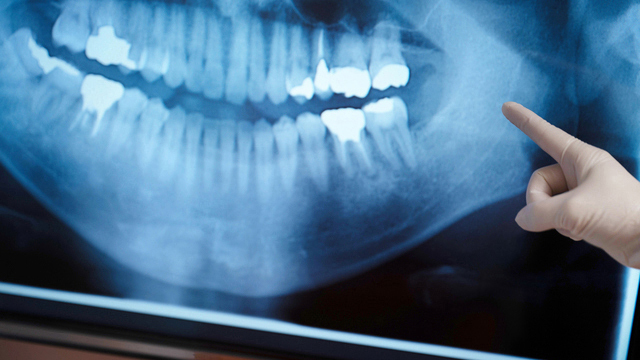

歯周病の検査

検査器具やレントゲンで、歯周病の進行度合いを調べます。

現在日本では、治療前の検査を簡略化してしまうケースが少なくありません。その点、当院は簡略化することはせず、精密な歯周病検査を実施しています。しっかりと検査をすれば、より効果的な治療計画を立てられるからです。